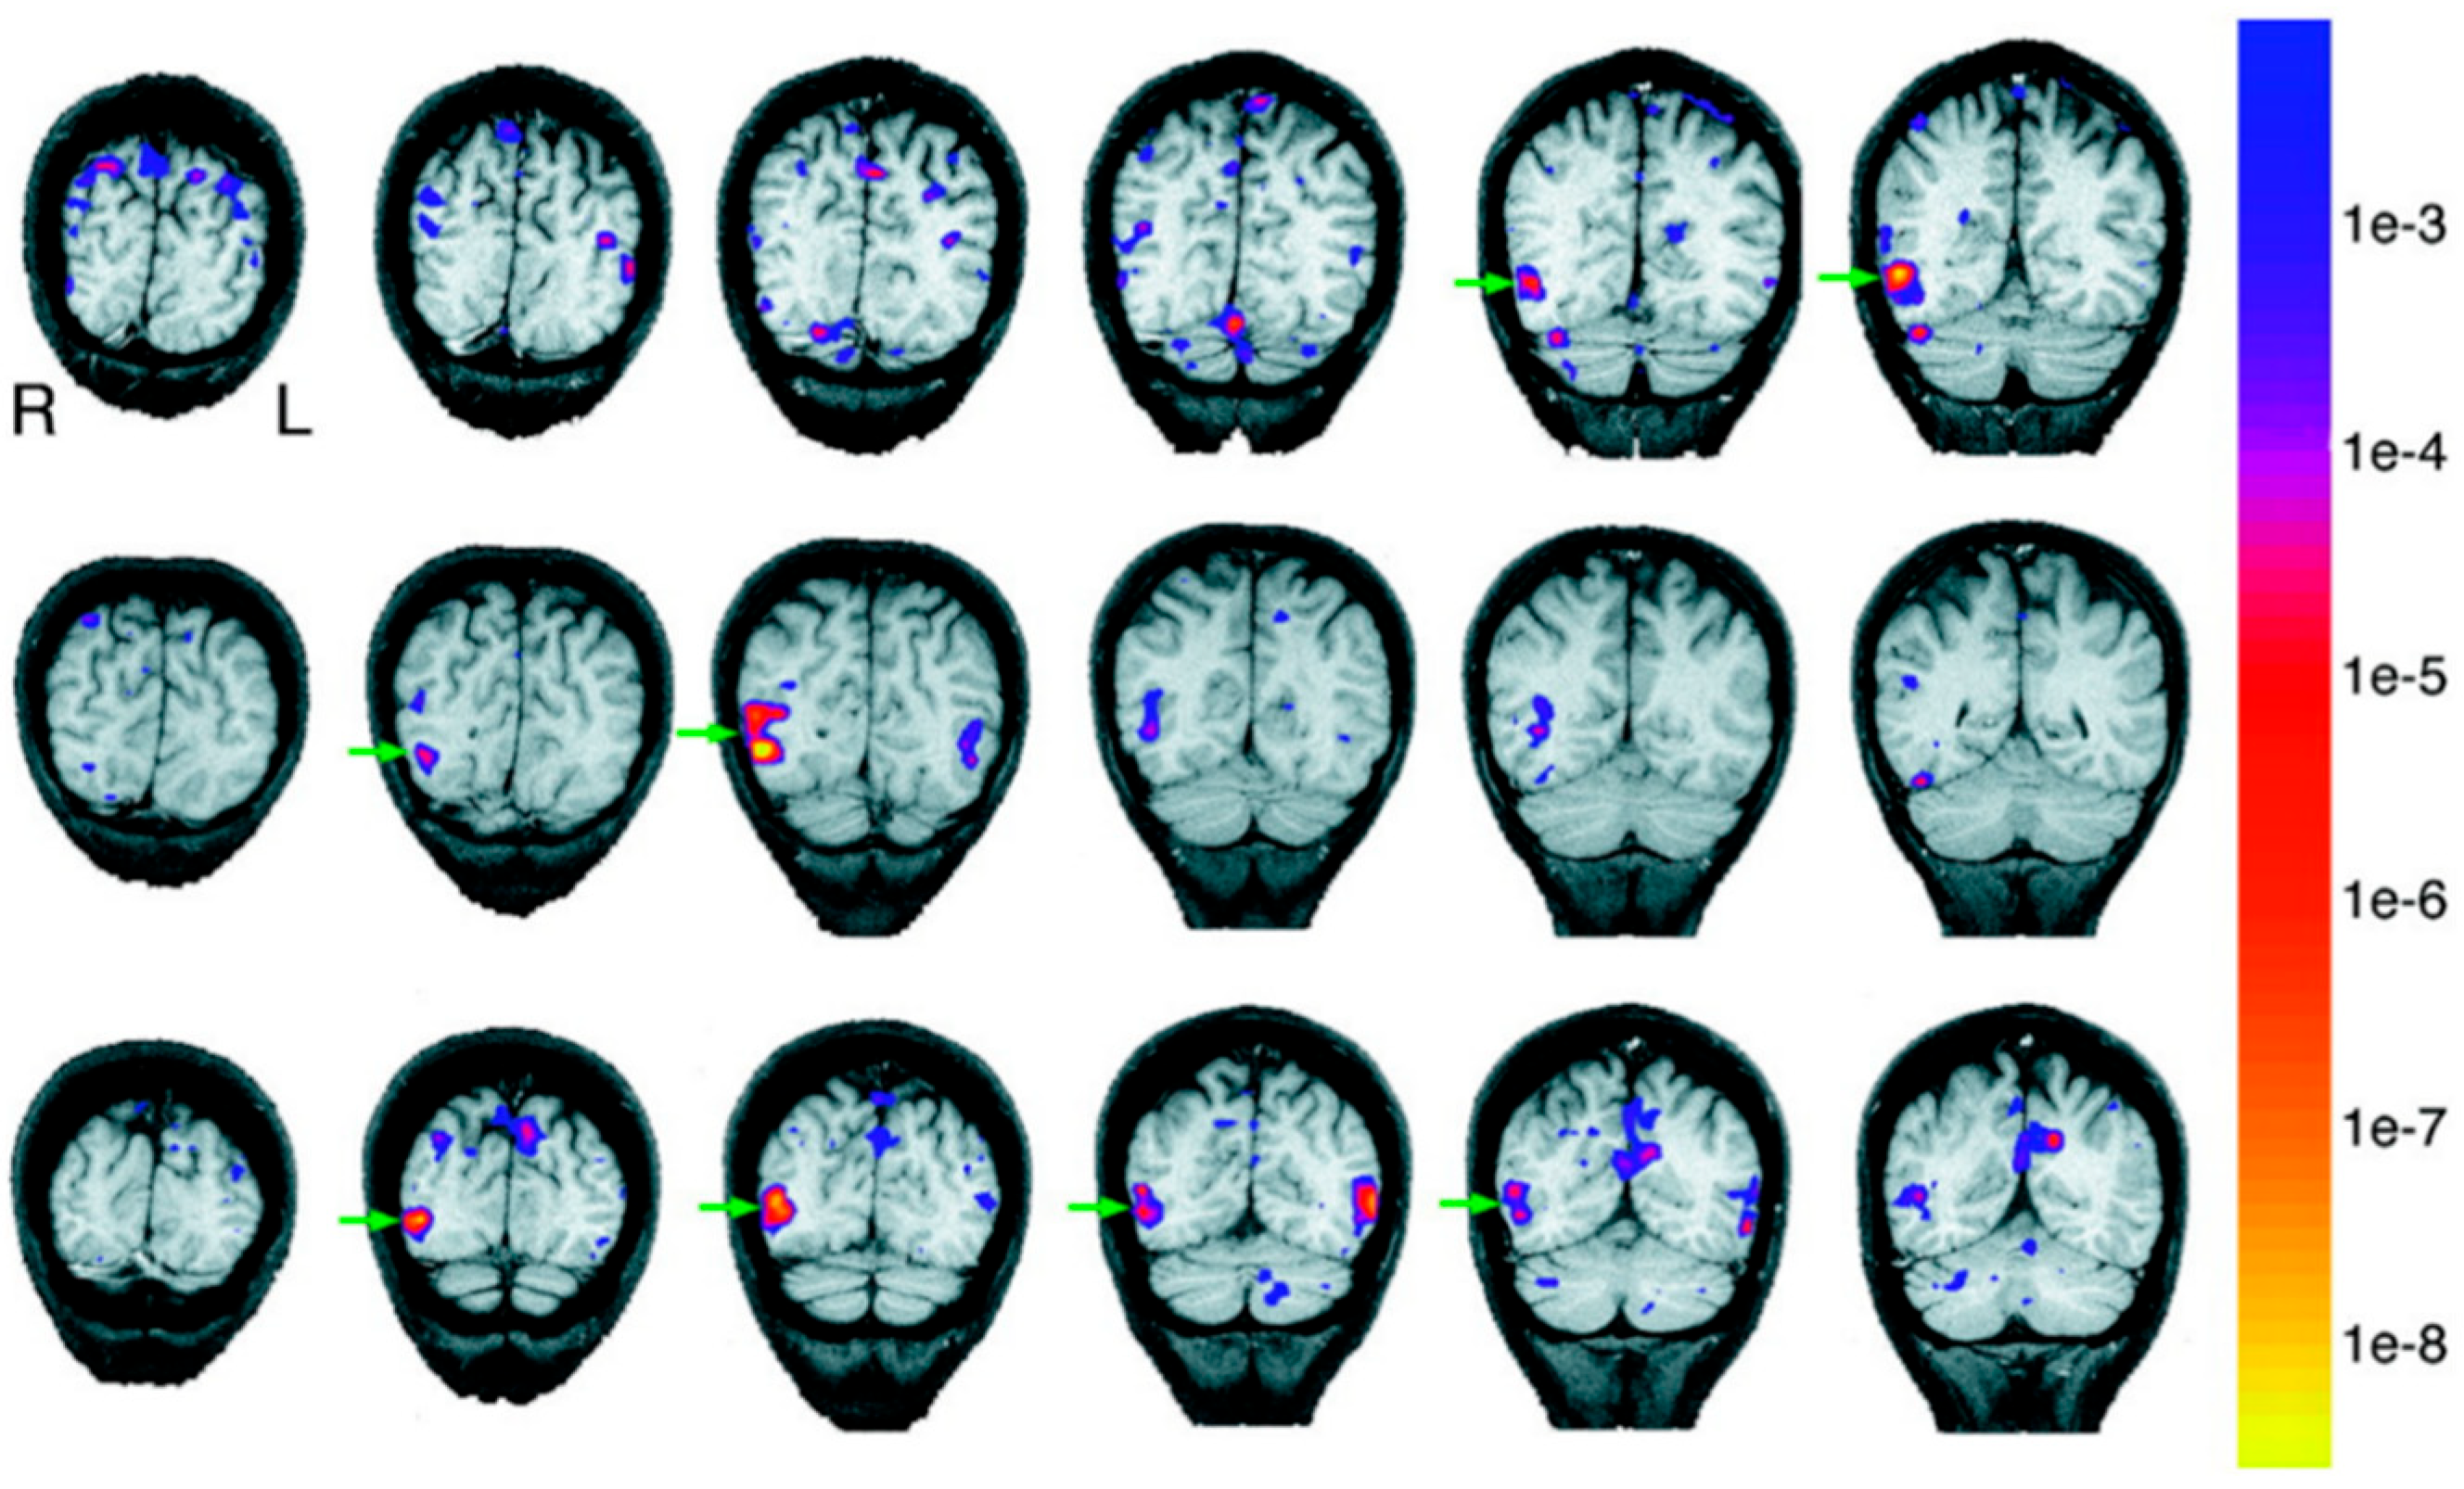

3. The Present